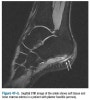

MRI 역시 불필요하지만 족저근막 종지부의 비후, 종골 돌기의 골수부종이 나타납니다(예후가 불량한 경우는 종골에서 족저근막 부착부 인접 부위의 골수종을 볼 수 있습니다).

MRI : 족저근막염(Plantar fasciitis)